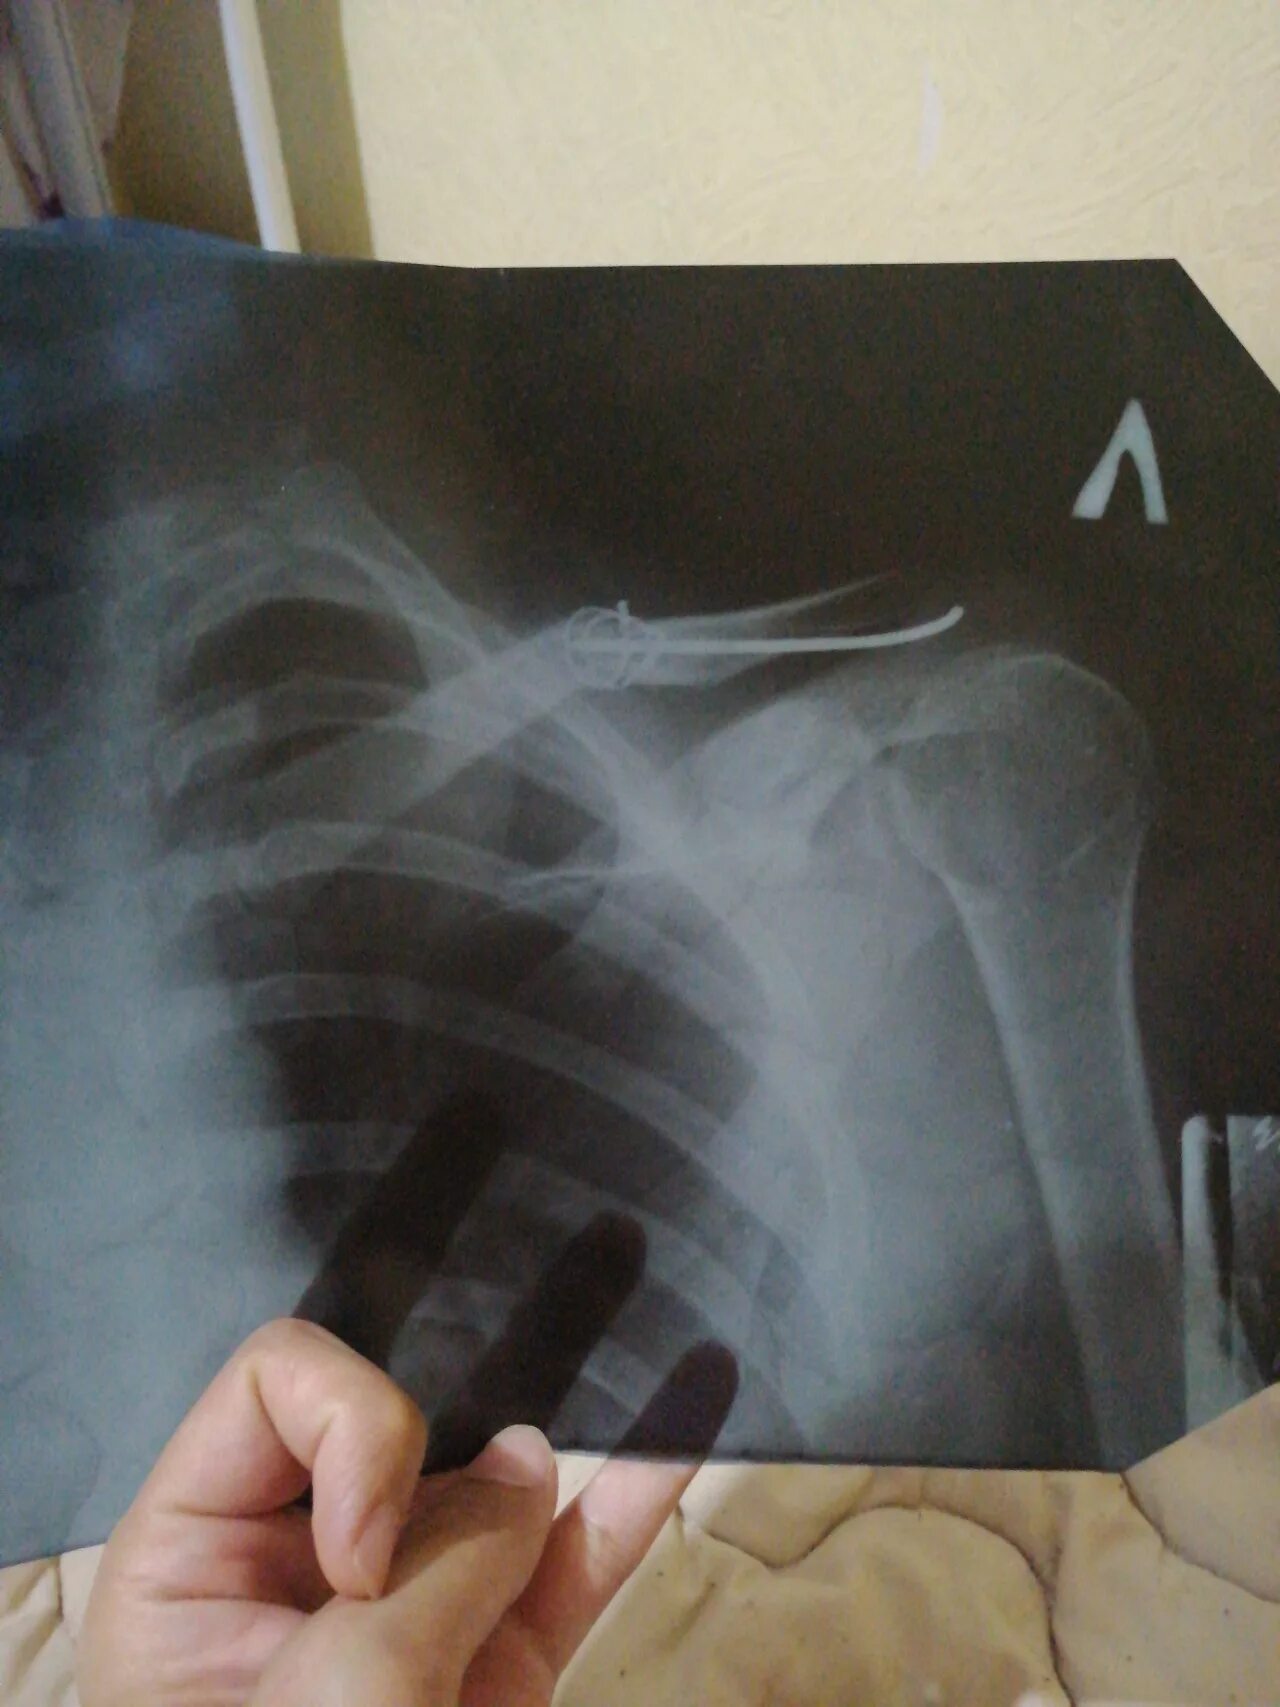

Сколько срастается ребро при переломе